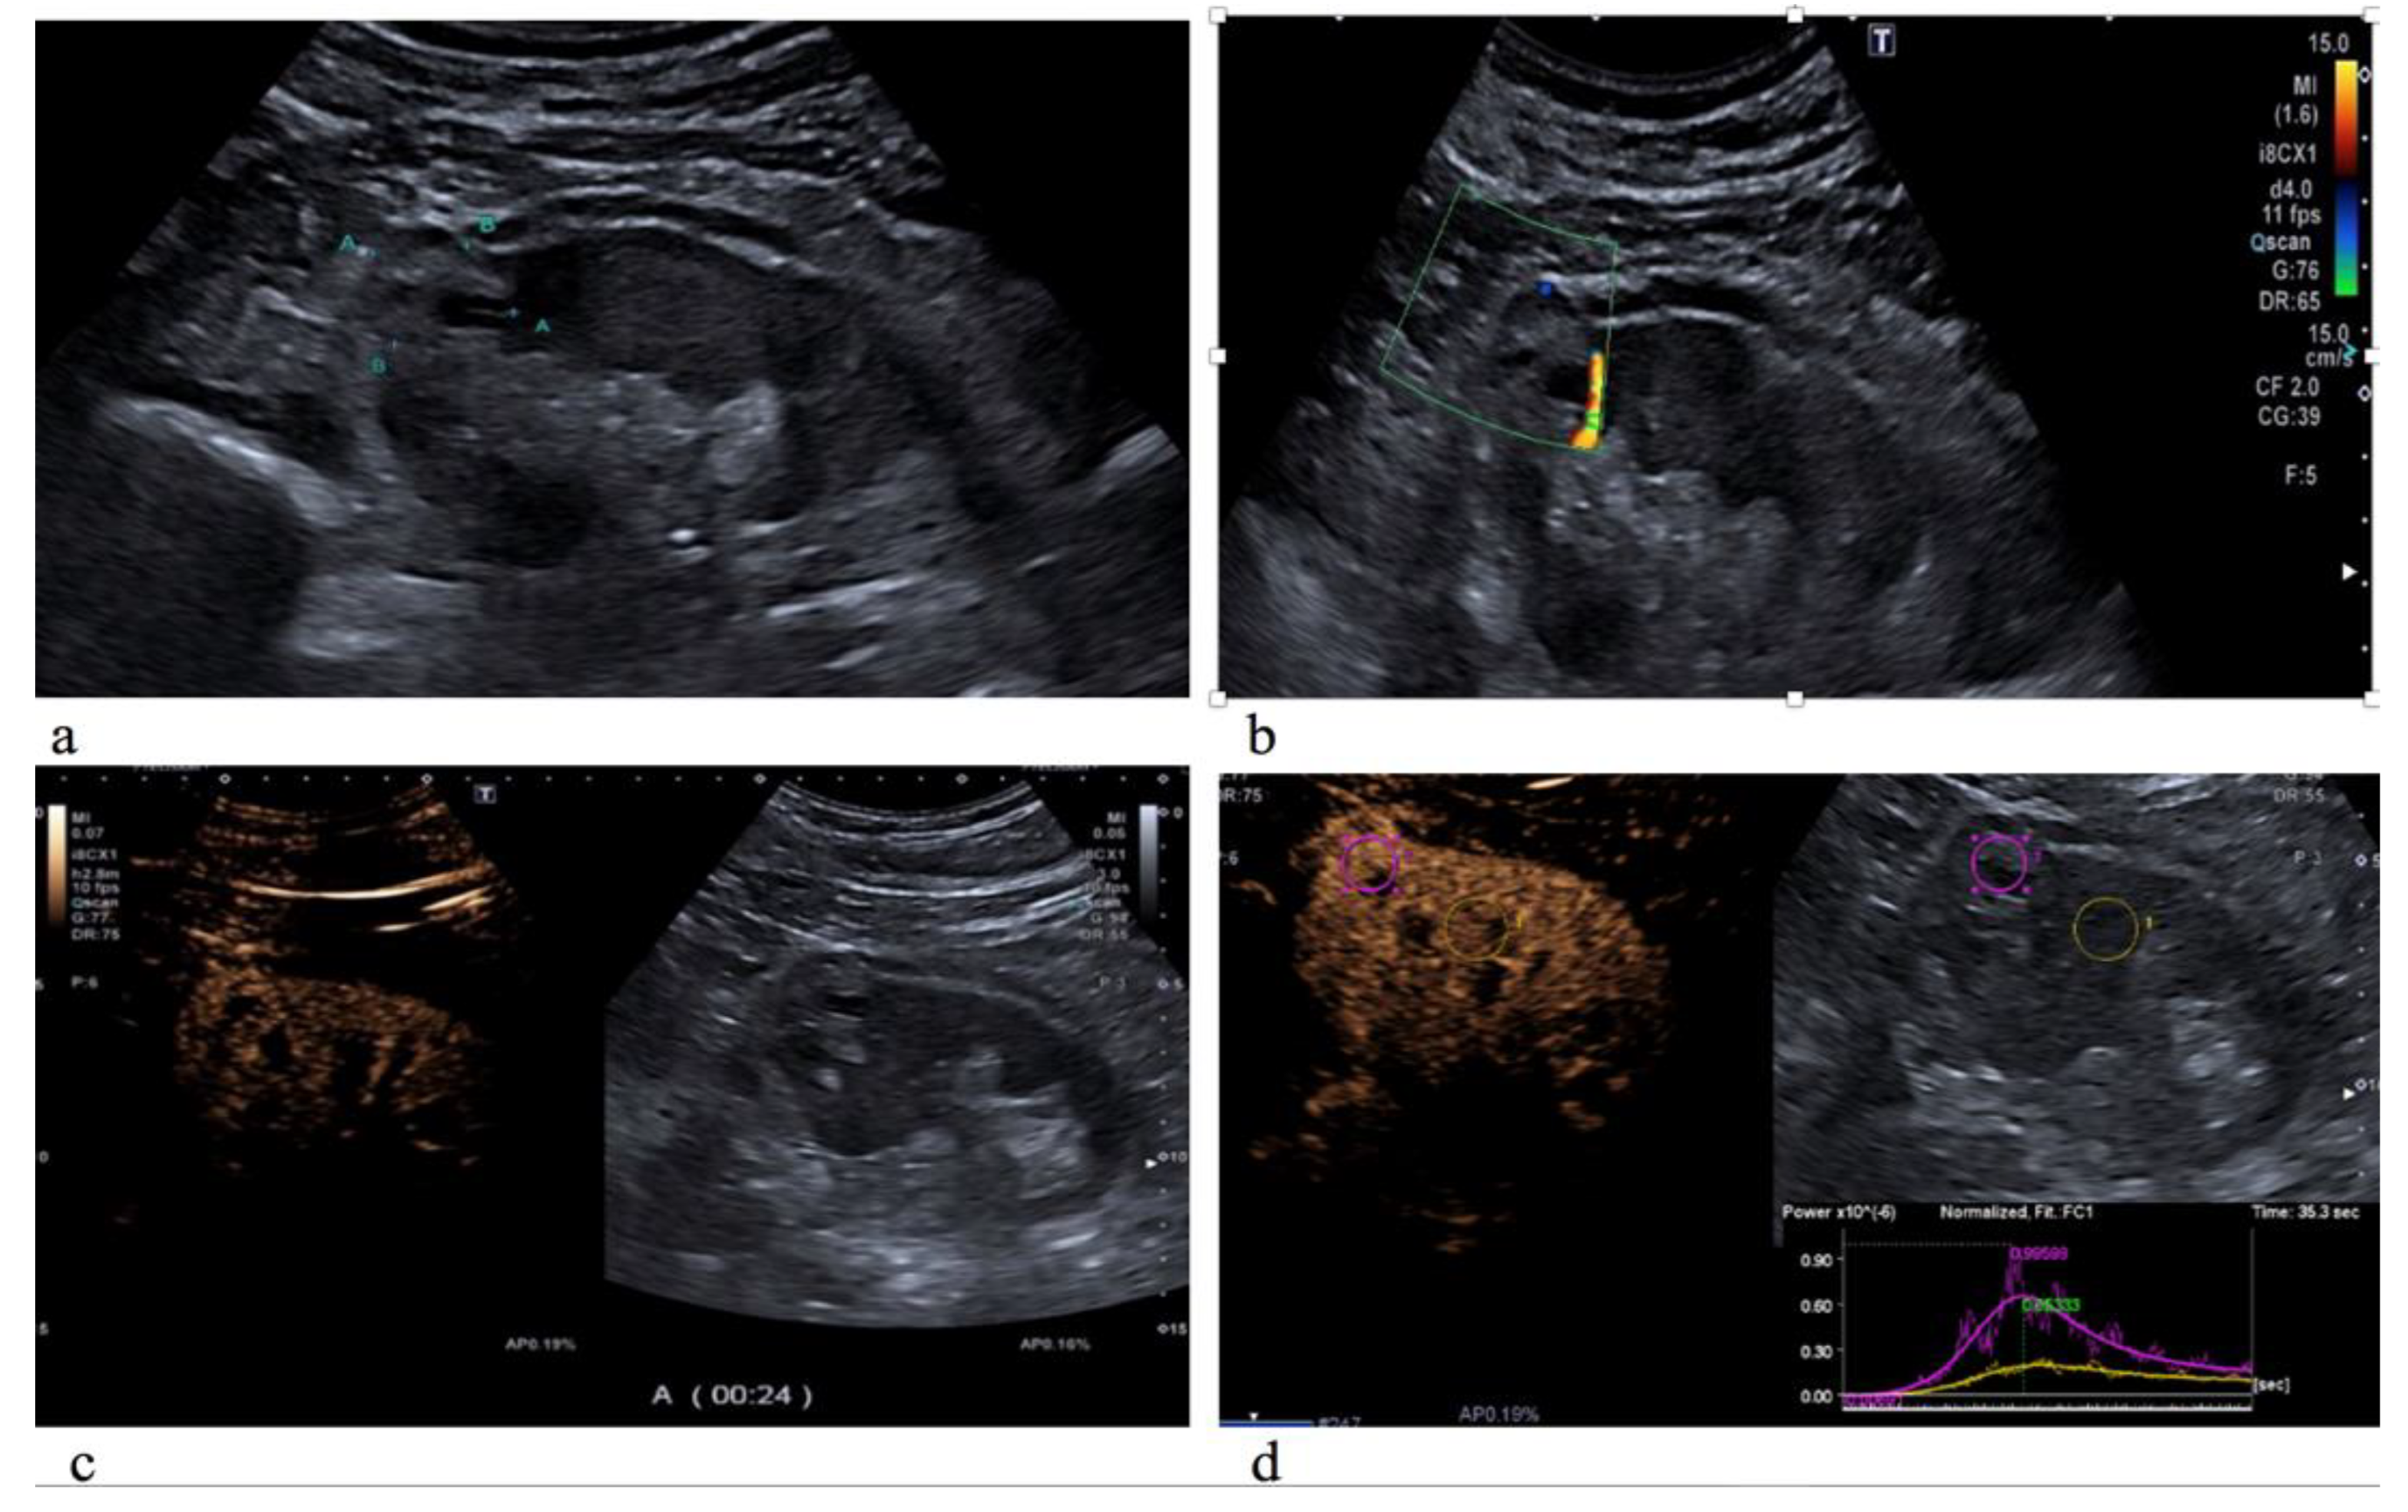

2.2. Imaging Acquisition and Interpretation

2.4. Qualitative CEUS Analysis

2.5. Quantitative CEUS Analysis